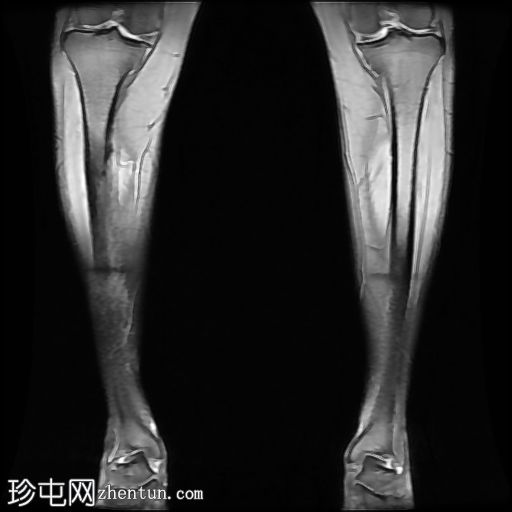

MRI

冠状位

STIR序列

内侧皮质可见一条低信号斜向皮质内线状影。

多发局灶性皮质内T2/STIR高信号病灶。皮质内可见一条线状信号异常区域。

邻近髓腔内广泛的骨髓水肿。

胫骨内侧缘骨膜水肿。

应力损伤部位皮质和骨髓增强扫描后强化。

轻度软组织水肿,无脓肿或积液。

腓骨正常,无骨髓水肿或皮质改变。

肌肉和肌腱正常。